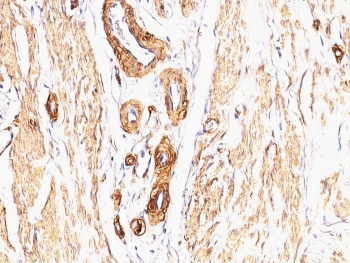

IHC: Formalin-fixed, paraffin-embedded Leiomyosarcoma stained with Smooth Muscle Actin antibody (clone SPM332).